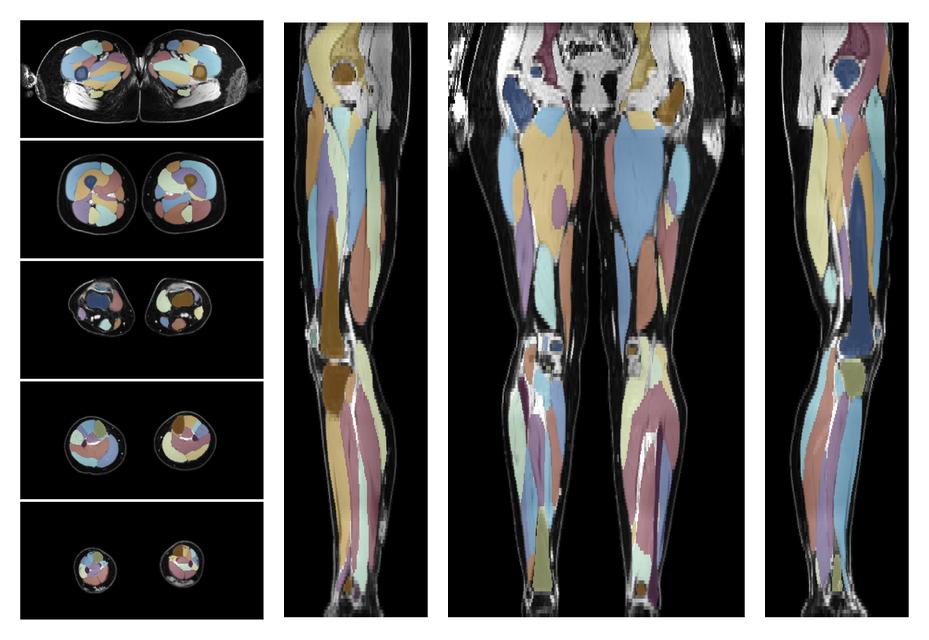

Muscle segmentation

Convolution neural network based (UNET) fiber automated muscle segmentation, for information look here».

- 3D volume render of automated muscle segmentation.

- Automated muscle and bone segmentation.

- 3D volume render of automated bone segmentation.